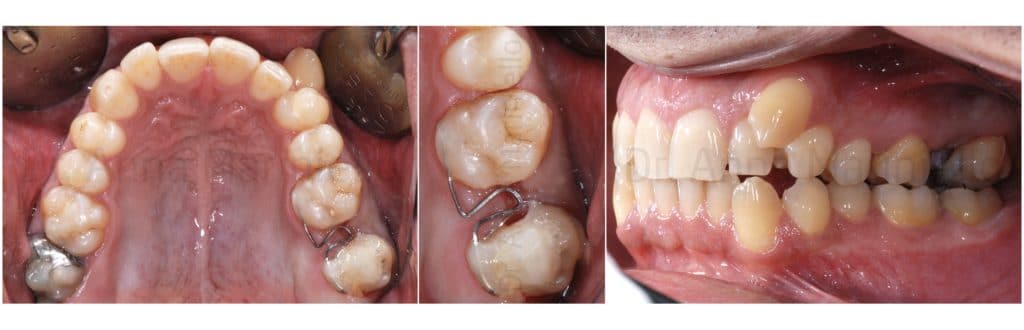

The patient, came to our attention, had a malocclusion characterized by:

- First class molar and canine on the right;

- Second class molar on the left;

- Complete absence of space for the left ectopic buccal canine;

- Upper and lower teeth crowding;

- Upper midline shifted 2,5 mm to the left;

- Overbite of 1 mm for 12, 3 mm for 11 and 21, 0 mm for 22.

- Overjet of 2,5 mm for 12, 2 mm for 11 and 21, 0 mm for 22.